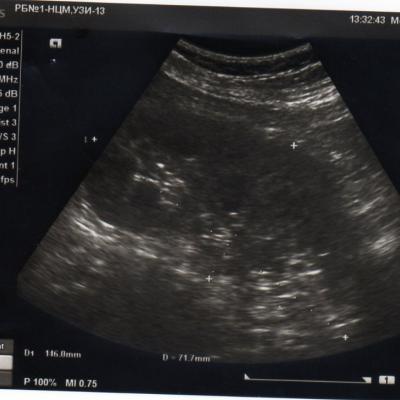

2 года назад у меня обнаружили кисту почки. в этом году УЗИ показала,что она исчезла. У меня одна единственная почка размером 146*71, увеличена. Киста размером 2,8*3,8 мм.сейчас почки болят.